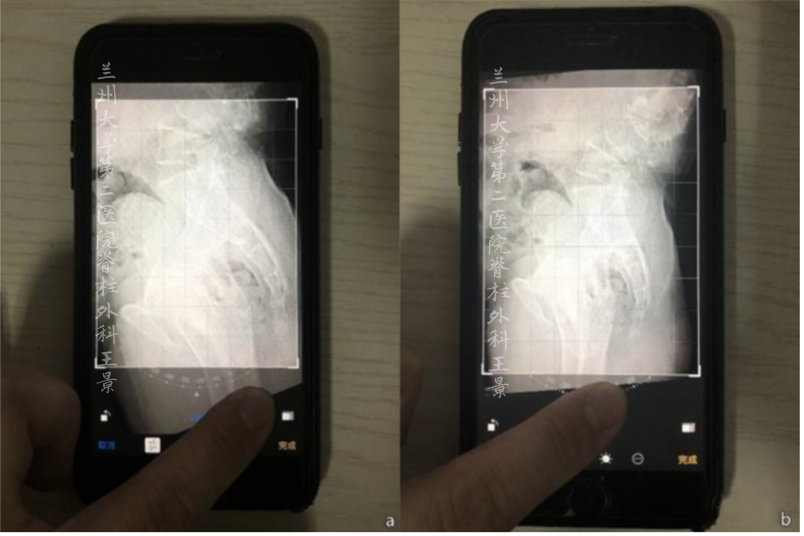

对着同一张片子

掏出iPhone,尽量正对拍摄

实际上稍微歪一点也没关系

打开照片,进入编辑模式

手指按着屏幕旋转照片

iOS自带的功能

图片旋转时会显示网格线及旋转角度

顺时针/逆时针旋转分别显示±°

精度为1°

如图所示旋转照片

S1上终板与水平线重叠/平行

旋转角度就是骶骨倾斜角

即SS=32°

再重新旋转图片

让股骨头中垂线与网格垂线重叠

旋转角度就是PT(-8°)

如果方法掌握熟练

或者为了大概估算

那么提前做的标记线可以省略

利用目测大概估计

从而达到快速测量目的